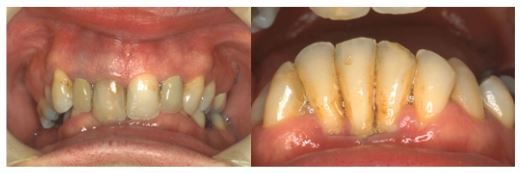

What is the likely cause of the gingival recession seen in the lower anterior sextant?

Traumatic overbite

3

Besides the lower anterior sextant, where else might you expect to see signs of a traumatic overbite?

Palatal gingivae of upper anteriors